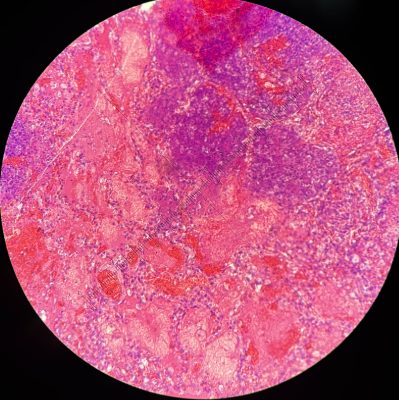

Lümfisõlme tuberkuloosne põletik